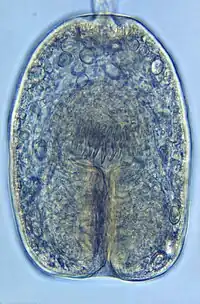

| Echinococcus granulosus protoscolex | |